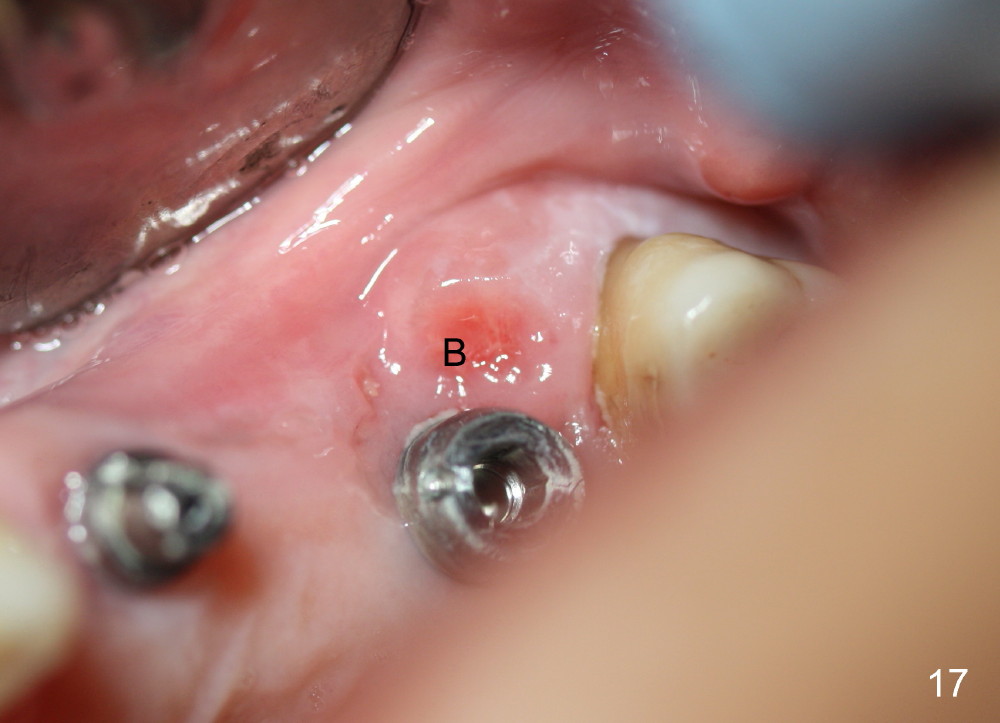

Two PAs are taken 5 months postop (Fig.15,16). Patterns of bone graft (*) between these PAs are different, which suggests presence of the graft buccal to the implant at the site of #14. Another piece of evidence of the graft is that the buccal socket heals (Fig.17 B) without implant thread exposure (Fig.19). These two implants are ready for definitive restoration (Fig.18-20). Fig.21 shows the final restoration 5 months post cementation.